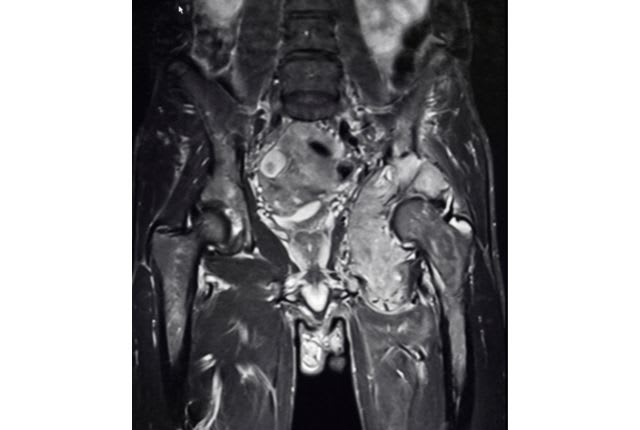

Dans un premier temps, des examens d’imagerie médicale sont effectués. Ils permettent de visualiser la taille de la tumeur et sa localisation précise. Une IRM (imagerie par résonance magnétique) ou un scanner est donc réalisé.

Après l’ostéosarcome, le sarcome d’Ewing représente la tumeur osseuse la plus fréquente. Elle touche surtout les enfants et les adolescents, mais peut également toucher les jeunes adultes. Il s’agit d’un cancer rare touchant moins de 100 personnes par an. Ce type de cancer osseux touche surtout les os plats comme le bassin, mais peut aussi toucher les os longs comme le fémur. Ce type de tumeur est lié à une altération génétique. Les jeunes adultes atteints de sarcome d'Ewing peuvent nécessiter des traitements plus agressifs en raison de la progression plus rapide de la maladie chez cette population. Le diagnostic précoce est donc essentiel pour améliorer les chances de guérison chez les jeunes adultes atteints de cette maladie.